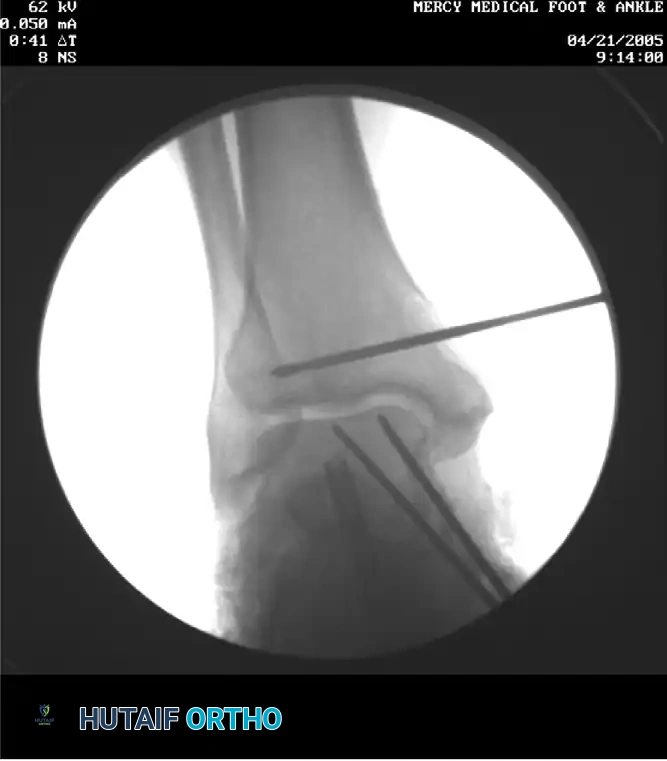

- Create a tibial tunnel by inserting a guidewire parallel to the joint surface at the level of the distal tibial physeal scar. The wire must be centered in the sagittal plane within the tibia.

- Confirm the guidewire position with multiplanar fluoroscopy.

- Drill a 6.5-mm tunnel to a depth of 25 mm over the wire.

- Advance a guidewire along this axis and confirm its position with anteroposterior and lateral fluoroscopy.

- With a cannulated drill, drill a 5-mm tunnel over the guidewire in an anterograde direction.

- Confirm the position of the guidewire with fluoroscopy, and create a 5-mm tunnel over the guidewire.